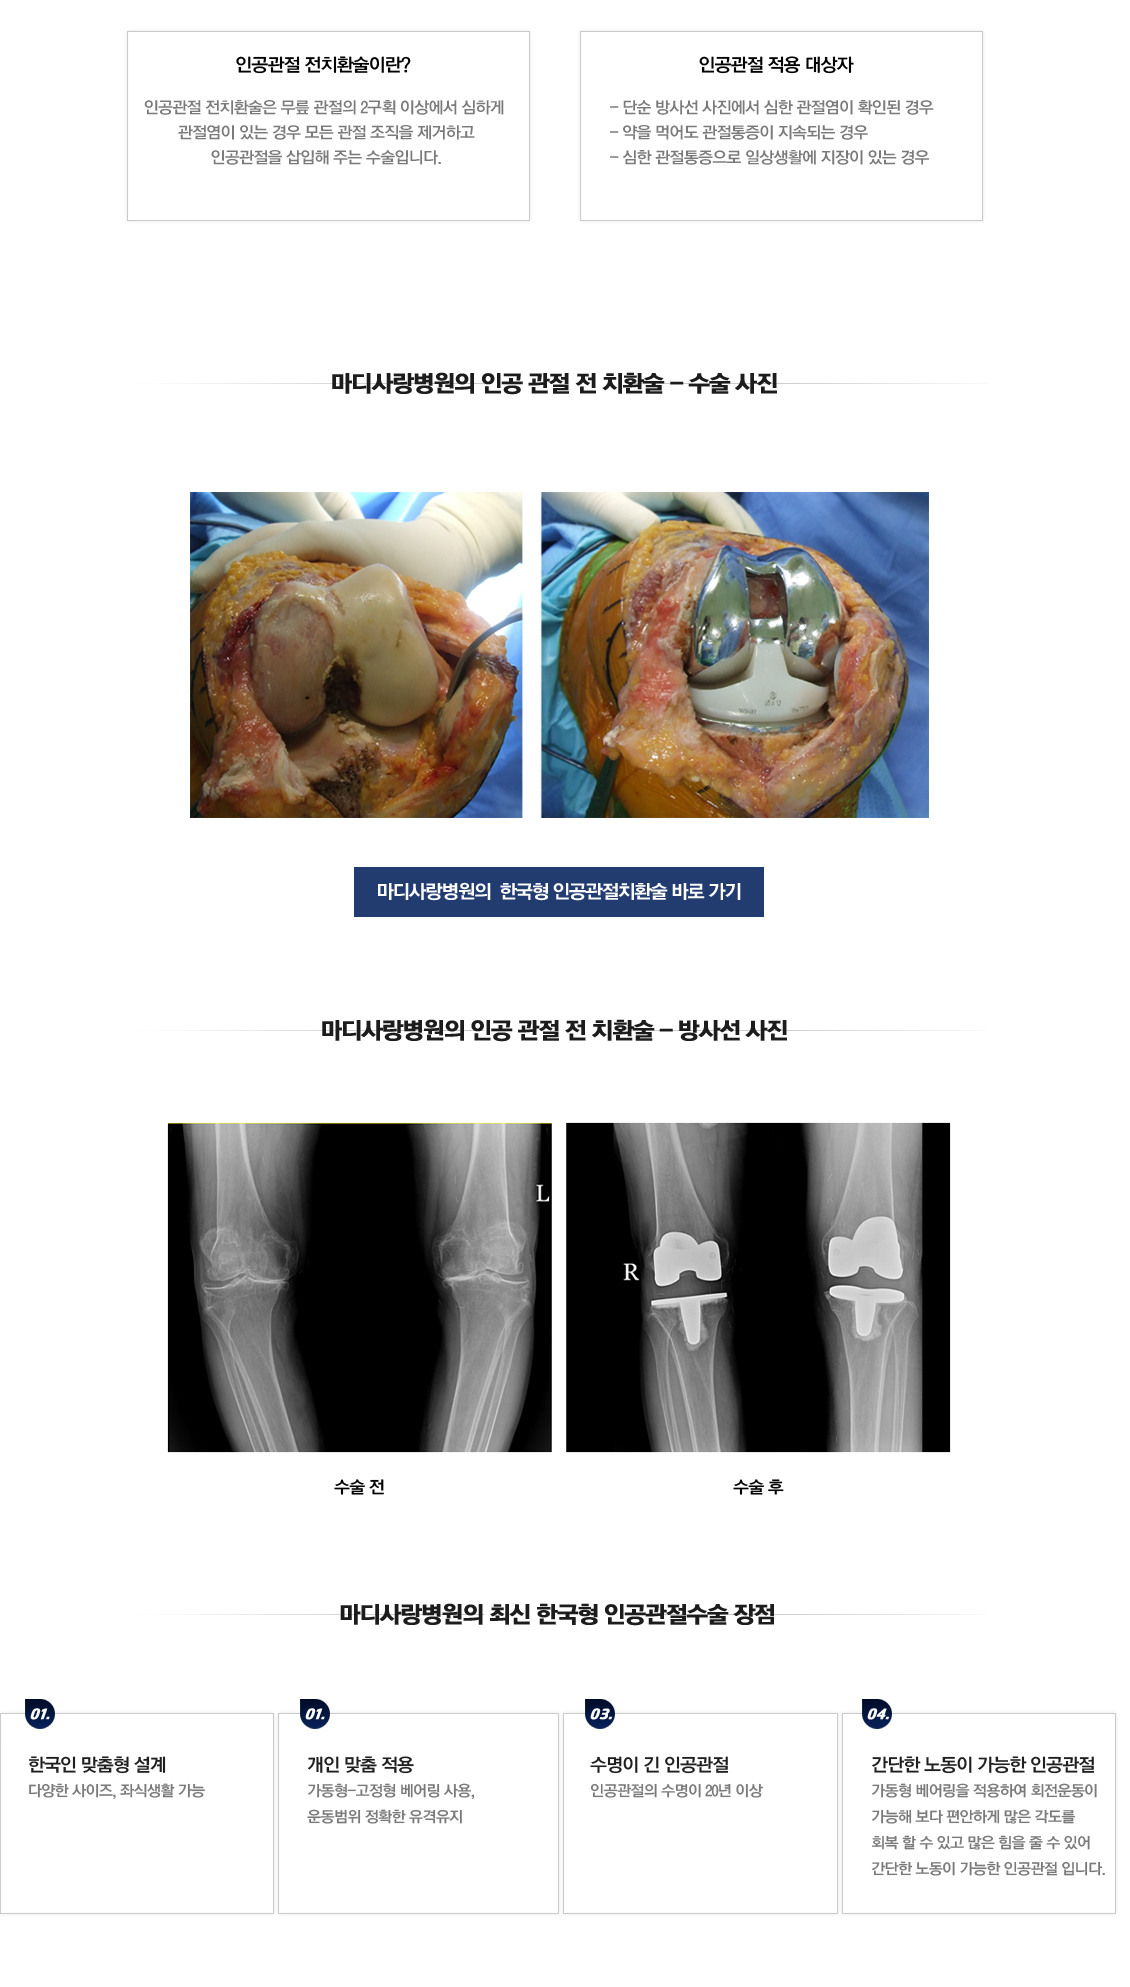

인공관절 전 치환술

무릎 인공관절 전치환술